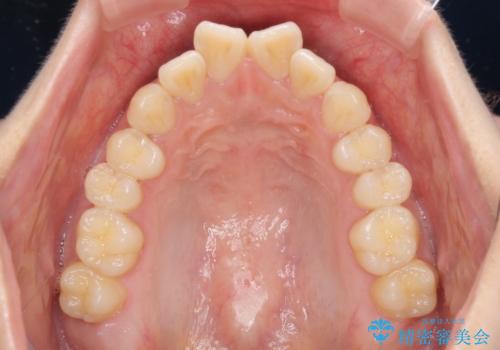

上下前歯の叢生をインビザラインできれいに

- 前歯のデコボコを気にして来院された患者様です。

前歯が重なっていることで口元が閉じにくくなっていたため、歯列全体の側方への拡大と、歯と歯の間を少し削ってスペースを獲得することとしました。

下顎前歯は後戻りを起こしやすいため、舌側を細いワイヤーで固定し、マウスピース型リテーナーで保定を行うこととしました。